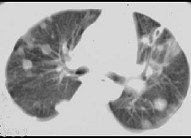

- 单项选择题女,32岁, 鼻梁双颊部出现红斑伴发热咳嗽2周,肘腕关节游走性疼痛, 请结合CT,选择最可能的诊断为 ( )

D、SLE肺部浸润